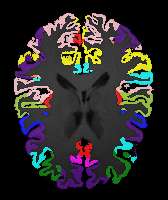

Results: All trained networks are evaluated using Dice overlap scores between predictions and the manual segmentations for the segmentation network, or between the warped moving segmentations and the target segmentations for the registration network. Tabs. 1 and 2 show results for the knee and brain MRI experiments respectively in Dice scores (%). Fig. 2 shows examples of knee MRI registrations and brain MRI segmentations.

Qualitative results: DA achieves more anatomically consistent registrations than the mono-networks on the knee (Fig. 2) and Brain MRI samples (see supplementary material).

Appendix 0.A Supplementary material

Moving

Target

Mono-0

Mono-21

DA-1

DA-21

Mono-65

Image

Manual Seg

DA-1

Mono-5

DA-5

Mono-200